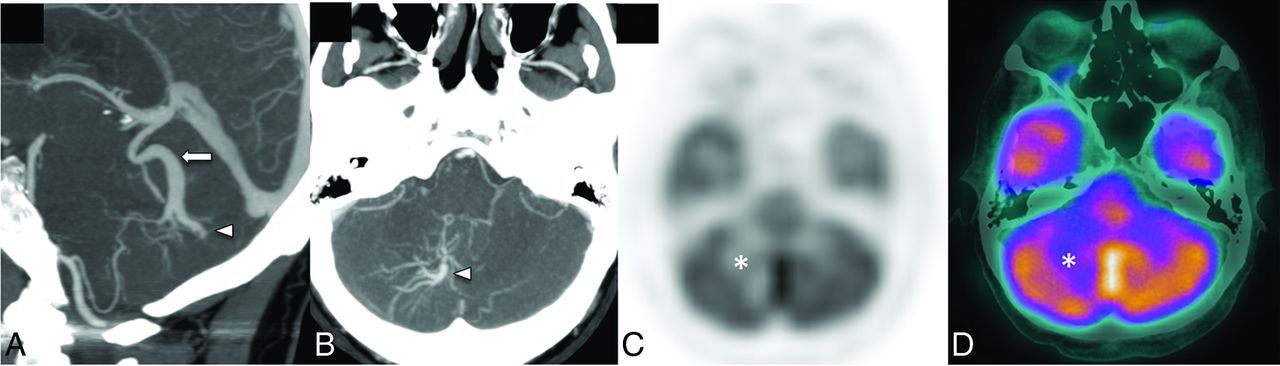

Basal ganglia and deep cerebellar nuclei are regions of the brain with higher metabolic demands. The presence of a DVA in these locations across time may lead to increased mineralization within the affected deep gray matter structure (Fig 4).20 Metabolic abnormalities can also be encountered in the venous drainage territory of a DVA. A small case series of 22 patients found that 76% of DVAs studied had metabolic changes on FDG-PET/CT scans in the form of hypometabolism, which was significantly more common in older patients (Fig 5).21 A subsequent larger study with 54 patients with 57 DVAs showed evidence of metabolic abnormalities in 38% of patients; in this study, hypometabolism was more common in DVAs draining gray matter rather than white matter.22 Hypometabolism has been reported in regions corresponding to neurologic symptoms; for example, hypometabolism was seen in the visual tracts in patients with visual symptoms and a corresponding DVA.23 Most interesting, structural abnormalities (ie, WMH) were not seen in these patients with abnormalities on functional images.21,22 Again, this finding is supportive of the notion that DVAs have a less robust venous drainage pathway.

A patient with headache and ataxia. CTA sagittal and axial MIP images (A and B) show a right cerebellar hemisphere DVA (arrowheads) with the collector vein (arrow) draining into the vein of Galen. Corresponding [18F] FDG-PET/CT attenuation-corrected image (C) and a fused PET/CT image (D) show moderate reduction of [18F] FDG uptake in the right cerebellar hemisphere in the venous territory of the large DVA (asterisk).